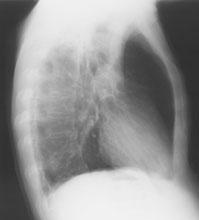

Thorax seitlich

Bild vergrössern